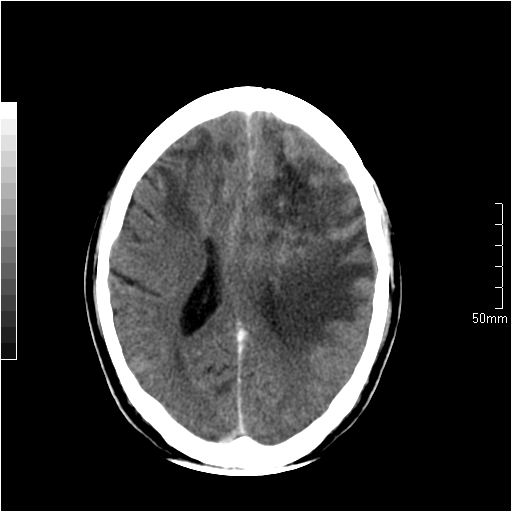

以下是引用天南地北在2007-6-25 12:39:00的发言:[br]有占位效应[br]支持术后复发

以下是引用zjzjr在2007-6-25 12:38:00的发言:[br]左侧复发,右侧转移。